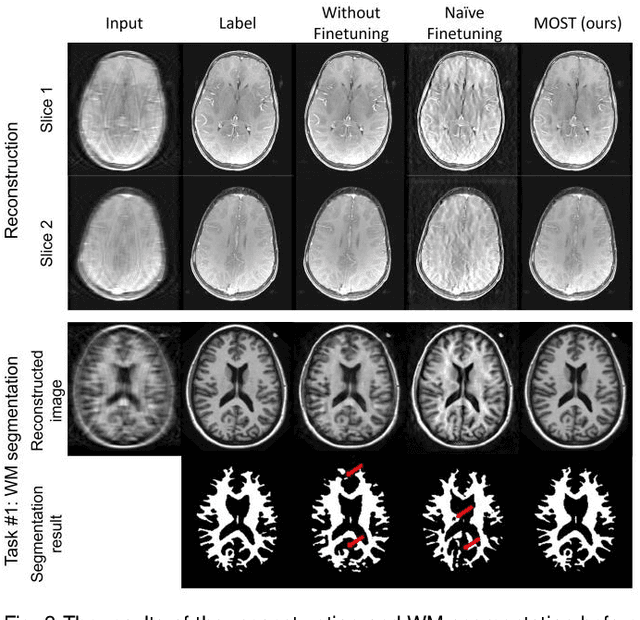

Abstract:Deep learning-based Magnetic Resonance (MR) reconstruction methods have focused on generating high-quality images but they often overlook the impact on downstream tasks (e.g., segmentation) that utilize the reconstructed images. Cascading separately trained reconstruction network and downstream task network has been shown to introduce performance degradation due to error propagation and domain gaps between training datasets. To mitigate this issue, downstream task-oriented reconstruction optimization has been proposed for a single downstream task. Expanding this optimization to multi-task scenarios is not straightforward. In this work, we extended this optimization to sequentially introduced multiple downstream tasks and demonstrated that a single MR reconstruction network can be optimized for multiple downstream tasks by deploying continual learning (MOST). MOST integrated techniques from replay-based continual learning and image-guided loss to overcome catastrophic forgetting. Comparative experiments demonstrated that MOST outperformed a reconstruction network without finetuning, a reconstruction network with na\"ive finetuning, and conventional continual learning methods. This advancement empowers the application of a single MR reconstruction network for multiple downstream tasks. The source code is available at: https://github.com/SNU-LIST/MOST